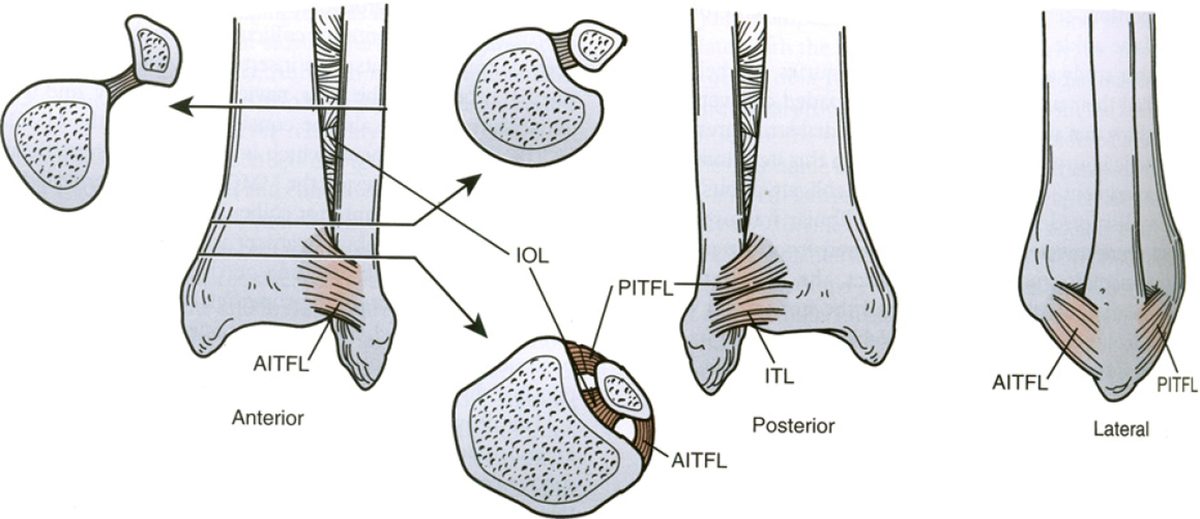

Связочный аппарат синдесмоза

Рис. 6. Схематическое изображение связок синдесмоза

Четыре связки формируют синдесмотический связочный комплекс: передняя нижняя большеберцово-малоберцовая связка (ПНБМс, AITFL), задняя нижняя большеберцово-малоберцовая связка (ЗНБМС, PITFL), большеберцово-малоберцовая межкостная связка (БММС, TFIL) и поперечная межберцовая связка (TTFL). Эти связки совместно с костными структурами обеспечивают целостность соединения между дистальными отделами большеберцовой и малоберцовой костей, противодействуя осевым, ротационным и трансляционным нагрузкам.

передняя нижняя большеберцово-малоберцовая связка (ПНБМс, AITFL)

ПНБМс проходит косо от переднего бугорка дистальной части большеберцовой кости (фрагмент Тиллау-Шапут), в среднем на 5 мм проксимальнее суставной поверхности, к переднему бугорку дистальной части малоберцовой кости. Связка имеет мультифасцикулярное строение — между пучками коллагеновых волокон расположена жировая ткань.

ПНБМс разделена на три части. Верхняя — самая короткая, начинается чуть проксимальнее переднего бугорка большеберцовой кости и прикрепляется чуть проксимальнее переднего бугорка малоберцовой кости. Средняя — наиболее прочная, проходит между передними бугорками большеберцовой и малоберцовой костей. Нижняя часть — самая длинная, распространяется дистальнее передних бугорков.

Добавочная передняя нижняя большеберцово-малоберцовая связка, известная как связка Бассетта (Bassett’s ligament), определяется в 21–92% случаев при анатомических препарациях и МРТ-исследованиях. Она проходит дистальнее и параллельно ПНБМс, не покрыта синовиальной тканью, является внутрисуставной структурой, пересекает проксимально-латеральный край голеностопного сустава и при тыльном сгибании контактирует с латеральным блоком таранной кости. Именно связка Бассетта может быть причиной переднелатерального импинджмента.

ПНБМс — самая слабая из четырёх синдесмотических связок и первой поддаётся нагрузкам, вызывающим наружную ротацию малоберцовой кости вокруг её продольной оси.

задняя нижняя большеберцово-малоберцовая связка (ЗНБМС, PITFL)

ЗНБМС — мощная связка, идущая от задней лодыжки большеберцовой кости к заднему бугорку малоберцовой кости в направлении от проксимально-медиального к дистально-латеральному. По форме и структуре она аналогична ПНБМс — мультифасцикулярна, состоит из множественных пучков коллагена с прослойками жировой ткани. Её нижняя часть, или поперечная связка (TTFL), расположена более горизонтально.

Поскольку ЗНБМС — толстая и прочная связка, чрезмерные нагрузки чаще приводят не к её разрыву, а к отрывному перелому задней лодыжки (фрагмент Фолькманна, Volkmann).

Поперечная межберцовая связка (TTFL)

Поперечная связка проходит горизонтально между проксимальным краем лодыжковой ямки малоберцовой кости и задненижним краем большеберцовой кости, иногда достигая задней поверхности внутренней лодыжки. Это толстая округлая связка, которая углубляет задненижний край большеберцовой кости и формирует аналог суставной губы (labrum analogue). Часть волокон задней таранно-малоберцовой связки (PTFL) сливаются с наиболее дистальными волокнами поперечной связки, образуя так называемый tibial slip, или межлодыжковую связку (IML).

Межлодыжковая связка (IML)

Межлодыжковая связка — отдельная анатомическая структура, обнаруживаемая почти всегда — в 81,8% из 77 препарированных образцов. IML начинается чуть проксимальнее начала задней таранно-малоберцовой связки в лодыжковой ямке и дистальнее начала поперечной связки. Она идёт параллельно поперечной связке, но всегда отделена от неё треугольным или четырёхугольным пространством, заполненным мягкими тканями.

Межкостная мембрана и межкостная связка

Межкостная мембрана проходит между большеберцовой и малоберцовой костями на всём их протяжении. В самом дистальном отделе она утолщается и формирует пространственную сеть пирамидальной формы, заполненную жировой тканью и крутыми пучками волокон, которые образуют межкостную связку. Большинство волокон идут от большеберцовой кости латерально-дистально и кпереди к малоберцовой кости, хотя некоторые волокна на передней поверхности имеют обратное направление.

Наиболее дистальные волокна прикрепляются к большеберцовой кости на уровне переднего бугорка и спускаются прямо к малоберцовой кости чуть проксимальнее таранно-большеберцового сустава. Наиболее проксимальные волокна прикрепляются к большеберцовой кости у верхушки вырезки. Межкостная связка отличается значительной вариабельностью: у одних людей она отсутствует, у других — отчётливо выражена, особенно при уплощённой вырезке большеберцовой и малоберцовой костей. Область под межкостной связкой обычно занята синовиальной складкой из таранно-большеберцового сустава.